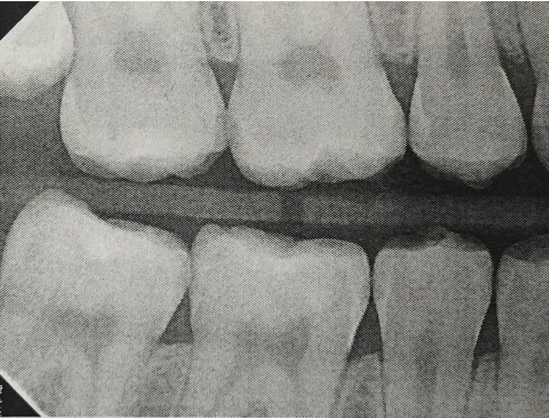

Fig 5. Three thin soft dental picks were used simultaneously for SDF proximal surface saturations in a teenaged patient (Fig 3). After 60 seconds, the treated regions were covered with 5% fluoride varnish (Fig 4). A comparison can be seen of pre-SDF-treatment bitewing films (Fig 5) and 8-month post-SDF bitewing films (Fig 6) for the patient shown in Fig 3 and Fig 4. Radiolucencies were similar or improved, except for contact of maxillary first and second molars.

Fig 6. Three thin soft dental picks were used simultaneously for SDF proximal surface saturations in a teenaged patient (Fig 3). After 60 seconds, the treated regions were covered with 5% fluoride varnish (Fig 4). A comparison can be seen of pre-SDF-treatment bitewing films (Fig 5) and 8-month post-SDF bitewing films (Fig 6) for the patient shown in Fig 3 and Fig 4. Radiolucencies were similar or improved, except for contact of maxillary first and second molars.

Fig 3. Three thin soft dental picks were used simultaneously for SDF proximal surface saturations in a teenaged patient (Fig 3). After 60 seconds, the treated regions were covered with 5% fluoride varnish (Fig 4). A comparison can be seen of pre-SDF-treatment bitewing films (Fig 5) and 8-month post-SDF bitewing films (Fig 6) for the patient shown in Fig 3 and Fig 4. Radiolucencies were similar or improved, except for contact of maxillary first and second molars.

Interproximal insertion of SDF is demonstrated in different patients in Figure 3 through Figure 11. Various diameters and brands of soft dental picks may be used depending on the closeness of the proximal surfaces and ease of insertion; for example, some picks are designed for use in wider spaces between teeth. This protocol also offers versatility. Figure 3, for example, shows the simultaneous use of three thin soft dental picks to saturate proximal surfaces with SDF in a teenaged patient; the treated regions were subsequently covered with fluoride varnish (Figure 4). This patient was initially treated in April 2019 (Figure 5), with an identical re-application 3 months later. As shown in Figure 6, the December 2019 bitewing film revealed good results with the possible exception of the contact regions of the maxillary first and second molars. New SDF application was completed in the December appointment.

The senior author's (TPC) private practice experience with soft-tip insertion of SDF into contacting proximal surfaces of teeth is that most beginning proximal surface caries lesions cease to progress, as evidenced by subsequent bitewing radiographic comparisons (Figure 3 through Figure 6, Figure 12 through Figure 18). The chances for success vary, however, depending on frequency of application, subsequent flossing by patients or adults flossing younger children, diet control, individual mouth chemistries, and use of fluorides for the topical effect. It must also be emphasized that office staff should make extensive efforts to inform children and parents that subsequent daily flossing is needed to accompany SDF treatments; otherwise, SDF applications will only delay the inevitable progression of caries. Flossing methods should be demonstrated for patients and for parents so they may see how to floss younger children. Showing them enlarged graphic photographs of flossing results may be helpful in this regard. Parents and patients should be made aware that if interproximal dental plaque accumulations persist without daily interruption by flossing, the acid insult will eventually take its toll on the proximal surfaces and caries lesions will progress to the point where restorative intervention may be required.